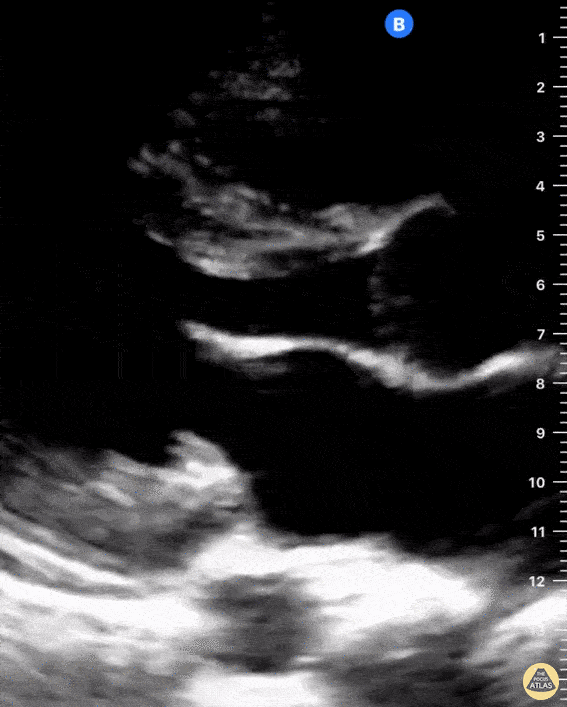

Seen here is a parasternal long axis view of the heart highlighting normal anatomy. You can see the left atrium, aorta, and right ventricular outflow tract, descending thoracic aorta, mitral valve and interventricular septum. Also notice the presence of a small amount of physiologic pericardial fluid. Pericardial fluid in this image is the hypoechoic shadow anterior to the descending thoracic aorta. There is no evidence of pleural effusion, however when present it would appear as a hypoechoic shadow inferior to the descending thoracic aorta. Shahad Al Chalaby, MD. PGY3, Highland Hospital, Alameda Health System Internal Medicine Residency Program @shahad_Chalaby